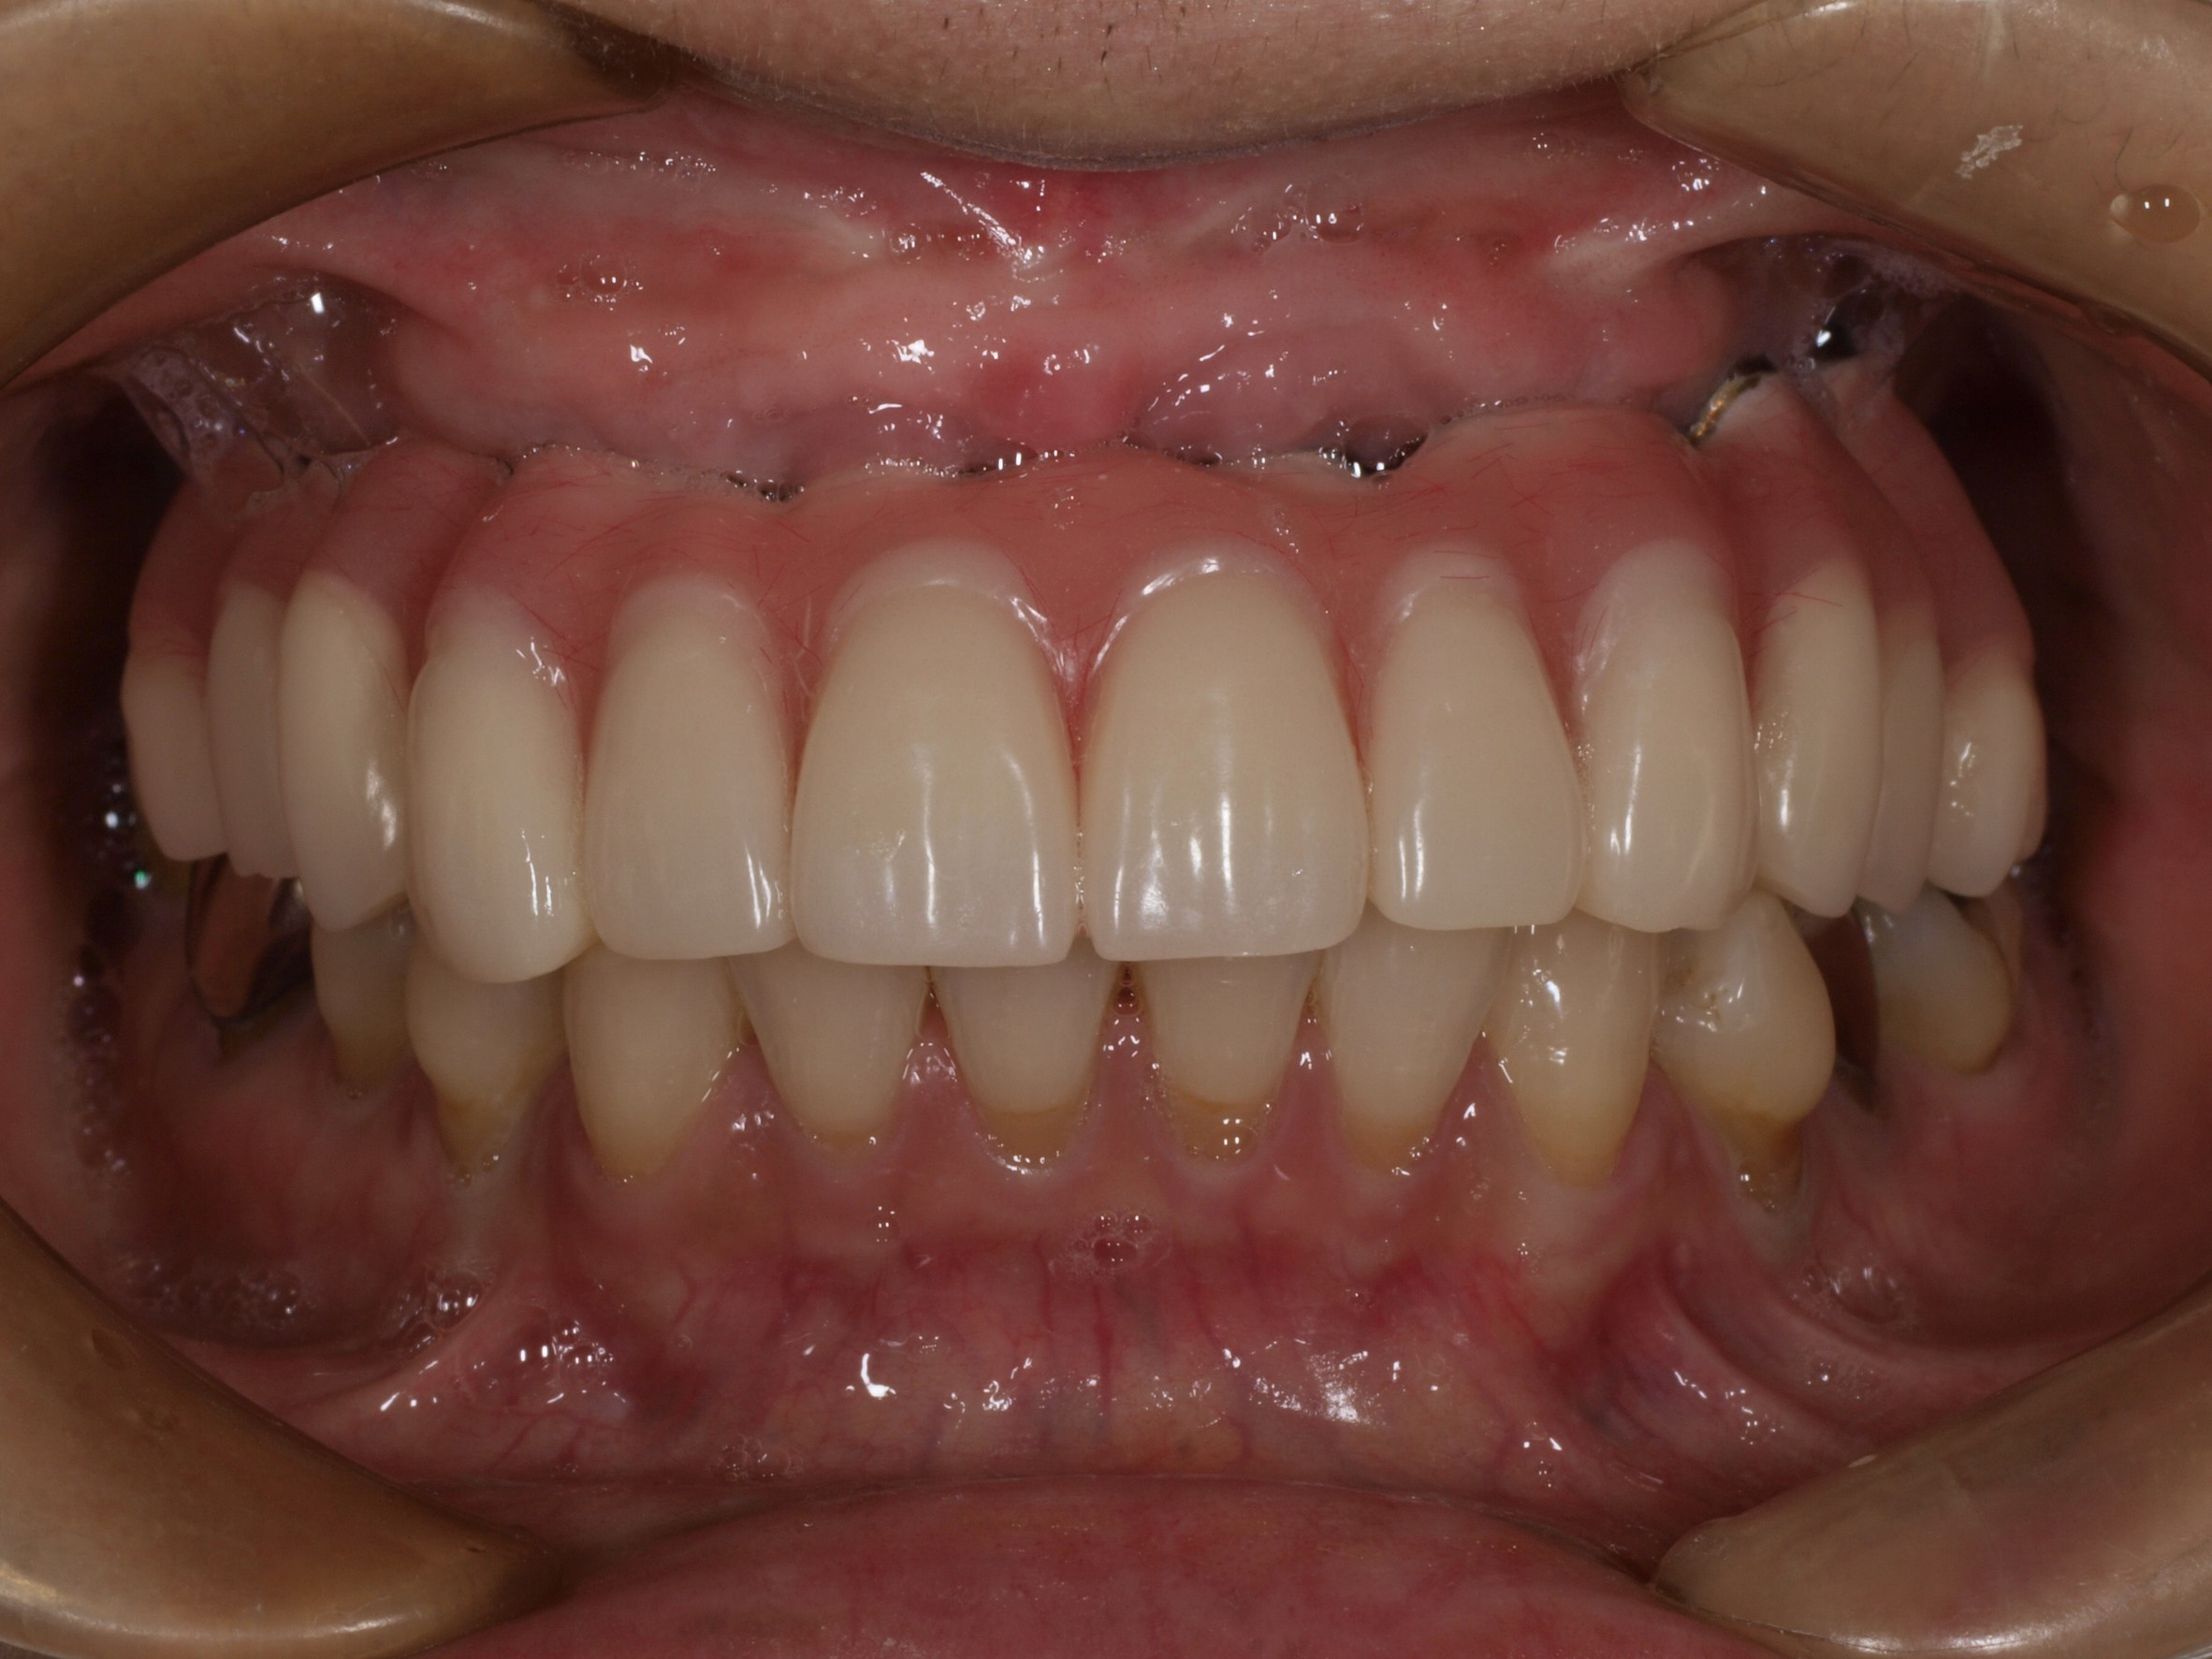

症例紹介

- 主訴

- 入れ歯が合わない。食べにくい。人生を豊かにしたい。

- 処置内容

- 上顎4本で12歯(オールオン4)、下顎4本5歯。

上下抜歯即時埋入、即時荷重(手術当日にインプラントの上に仮歯装着)

- 治療費用

- 上顎:約290万(税込)、下顎:約210万円(税込)

- 治療期間・通院回数

- 上顎:9か月/9回

下顎:6か月/7回

- リスク

- 術後の腫れ、痛み(ピークは3日後、1週間で軽減)

上部構造物、仮歯の破折、人工歯根脱落リスクがあります